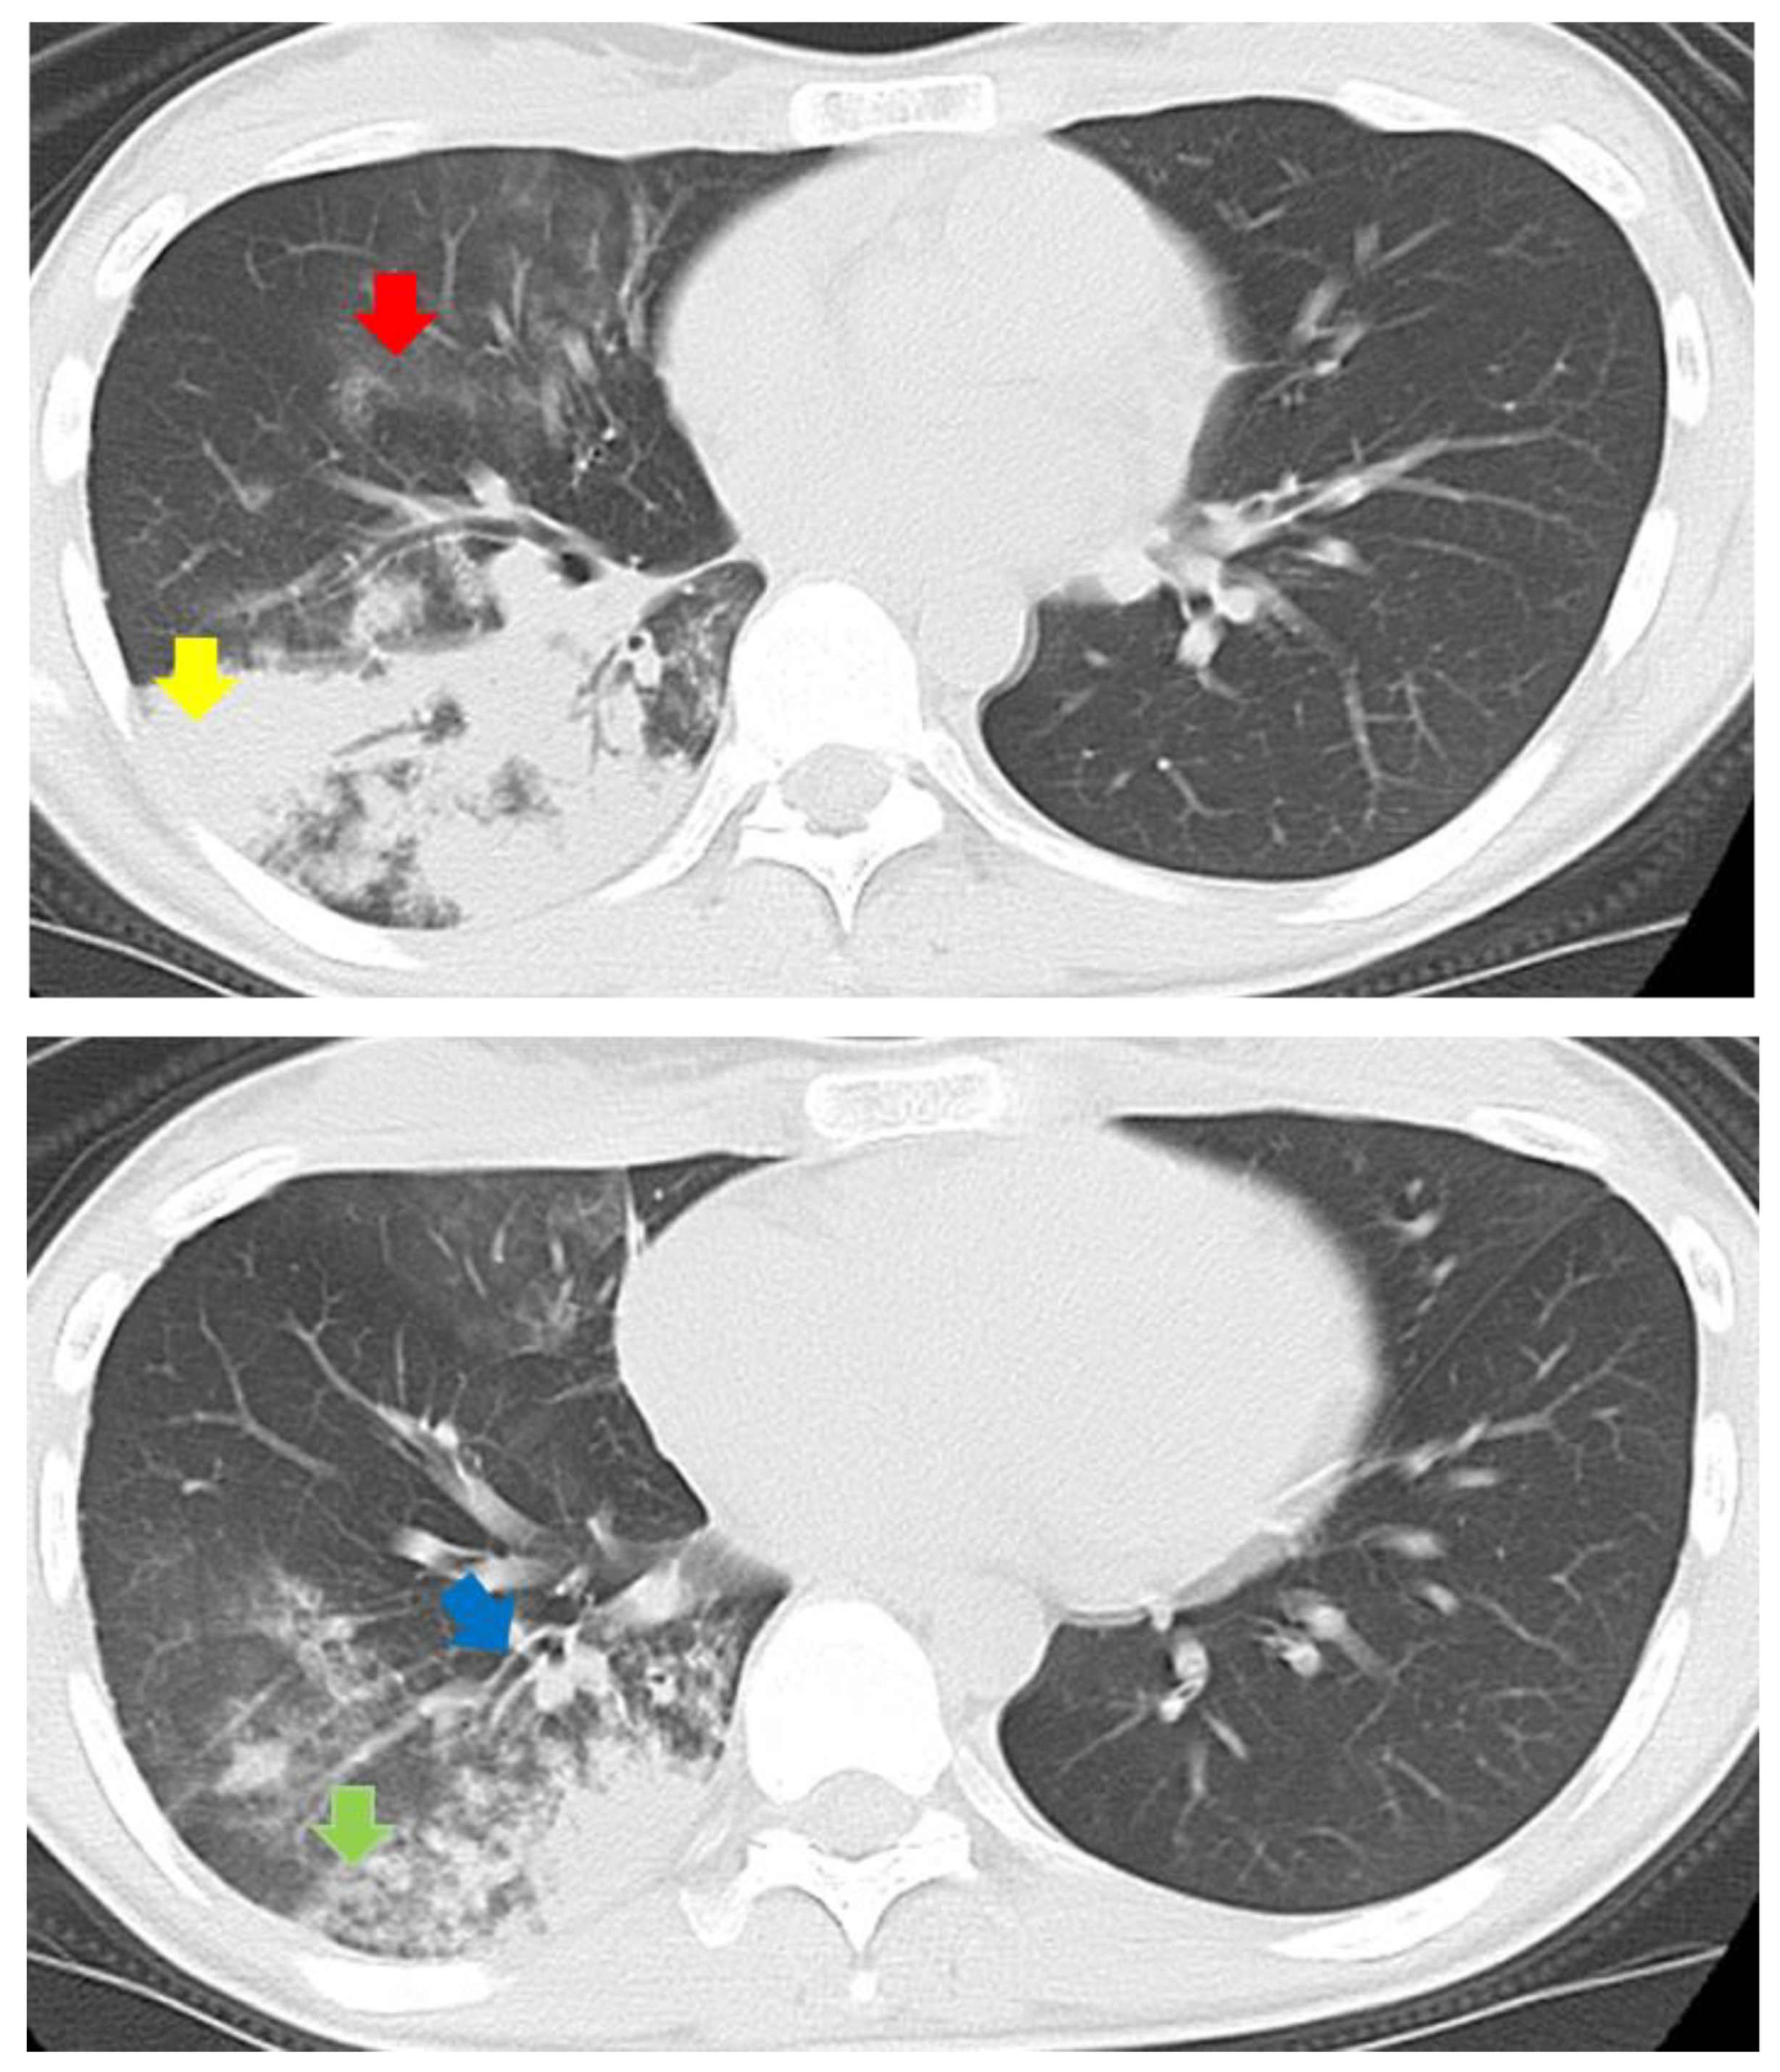

| Centrilobular nodules | 9 (90) | 7 (54) | 8 (57) | 5 (28) | 0.0171 |

| Branchial wall thickening | 10 (100) | 9 (69) | 10 (71) | 11 (61) | 0.1670 |